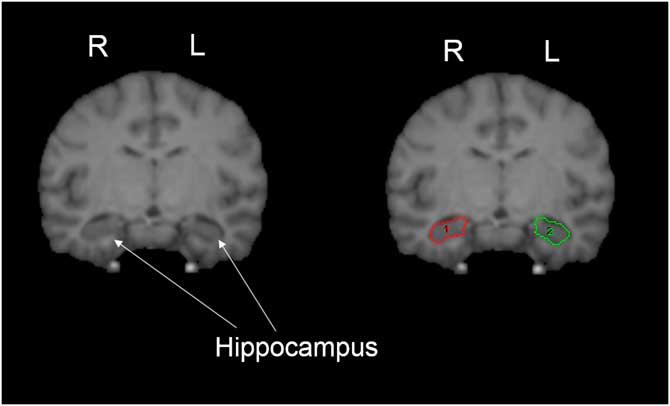

We quantified the hippocampus following procedures previously employed with humans and chimpanzees (De Bellis et al., Reference De Bellis, Keshavan, Clark, Casey, Giedd, Boring and … Ryan1999; Freeman, Cantalupo, & Hopkins, Reference Freeman, Cantalupo and Hopkins2004; Gosche, Mortimer, Smith, Markesbery, & Snowdon, Reference Gosche, Mortimer, Smith, Markesbery and Snowdon2001; Hopkins, Lyn, & Cantalupo, Reference Hopkins, Lyn and Cantalupo2009; Pegues, Rogers, Amend, Vinogradov, & Deicken, Reference Pegues, Rogers, Amend, Vinogradov and Deicken2003; Sherwood et al., Reference Sherwood, Cranfield, Mehlman, Lilly, Garbe, Whittier and … Holloway2004, Reference Sherwood, Gordon, Allen, Phillips, Erwin, Hof and Hopkins2011). The hippocampus was primarily traced in the coronal plane, but multiplanar views were used when it was difficult to distinguish landmarks in one plane of view. The anterior border of the hippocampus was defined as the first slice in which the inferior horn of the lateral ventricle was visible. The posterior border was the slice anterior to the crus of the fornix. This excluded the isthmus of the cingulate gyrus and the parahippocampal gyrus. The medial border of the hippocampus was defined by WM represented by the alveus, or the ambient cistern if the alveus could not be seen. The ambient cistern and alveus were often difficult to distinguish from the hippocampus. In such cases, several tactics were used, including enlarging the image of the slice to distinguish WM, and also comparing anterior and posterior slices to determine if WM was present. Laterally, the hippocampal border was the temporal horn of the lateral ventricle and the WM of the parahippocampal gyrus was used as the inferior border. The choroid fissure was used as the superior border of the hippocampus. The definition of the hippocampus included the cornus ammonis, dentate gyrus, subiculum, subicular complex, and hippocampus, proper. However, the fimbria and alveus were not included in the measurement of the hippocampus. As the delineation of the amygdala from the hippocampus was only based on the inferior horn of the lateral ventricle, rather than the alveus, a small portion of the amygdala may have been included in hippocampus measurements (Figure 2).

Figure 2 Pictorial representation of hippocampus. The white matter of the parahippocampal gyrus was used as the inferior border, and the choroid fissure was used as the superior border of the hippocampus. The definition of the hippocampus included the cornus ammonis, dentate gyrus, subiculum, subicular complex, and hippocampus, proper (shown on right image). ROIs for right (1) and left (2) shown in red and green, respectively. For more details, see hippocampus region of interest tracing methods text.